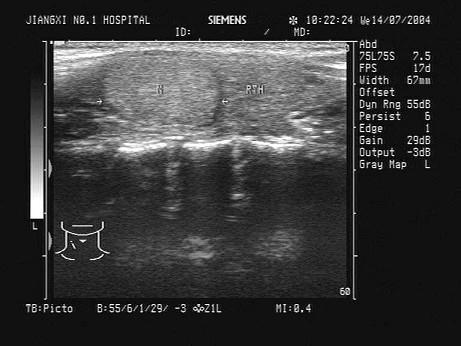

问题 患者,女,35岁,发现颈部稍大3年,无明显不适。甲状腺超声见右侧甲状腺一单发异常光团,声像图如下,最可能的诊断为?(?)

选项 A.甲状腺癌 B.结节性甲状腺肿 C.甲状腺炎 D.甲状腺腺瘤 E.甲状腺囊肿

答案 D